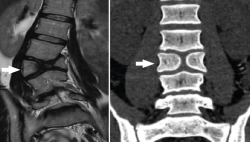

Figura 11. Malformación vertebral en resonancia y tomografía axial computarizada.

La TAC visualiza con bastante precisión el tejido óseo, siendo claramente superior a la RM para ello. También permite visualizar los tejidos blandos intra- y paraespinales, aunque la RM es muy superior en la evaluación de estos tejidos, por lo que está siendo desplazada por esta para el estudio de los problemas discales, degenerativos y radiculomedulares (Figura 11).